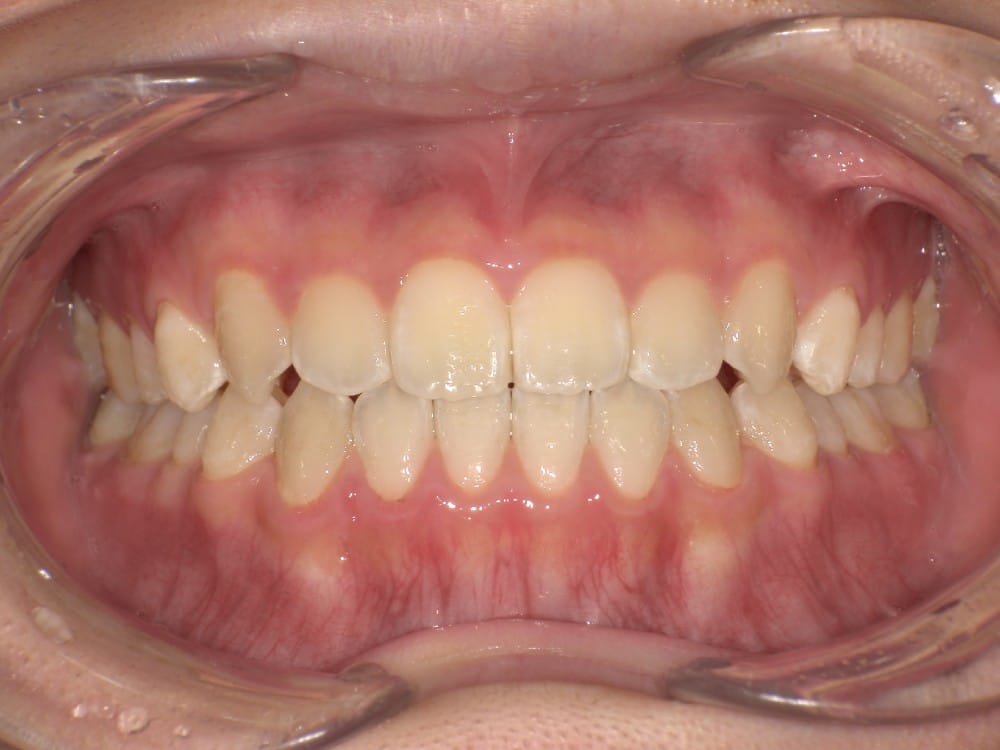

治療後の写真

矯正治療によって前歯の被さりを改善することで、口元の突出感が減り、横顔がやわらかい印象に変化しました。

<治療前後の比較です>